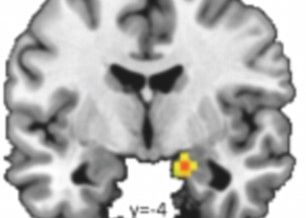

Celebra expresie "barbatii nu inteleg femeile" are si o acoperire stiintifica dupa ce oamenii de stiinta au facut publice rezultatele unor teste in timpul carora subiectilor le-a fost analizata activitatea creierului. Barbatii au privit mai multe fotografii cu expresia ochilor, cel mai greu fiindu-le sa "ghiceasca" ce exprima privirile femeilor. Partea din creier numita amygdala (despre care se crede ca responsabila pentru empatii) este mult mai activa cand barbatii privesc la alti barbati decat la femei.